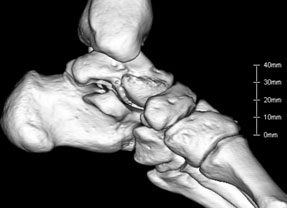

CTとはX線を使って骨の断面像を作成する検査法で、レントゲン写真より何倍もの情報を正確に得ることができることができます。また3次元画像で人体の構造を立体的に表示できるようになり、実際の診断や患者様への説明においても大変わかりやすいものとなっています。実際に検査を受けている時間は10分程度ですので、精密検査でありながら、すぐに施行することができる”敷居の低い”検査として、日夜大活躍しています。